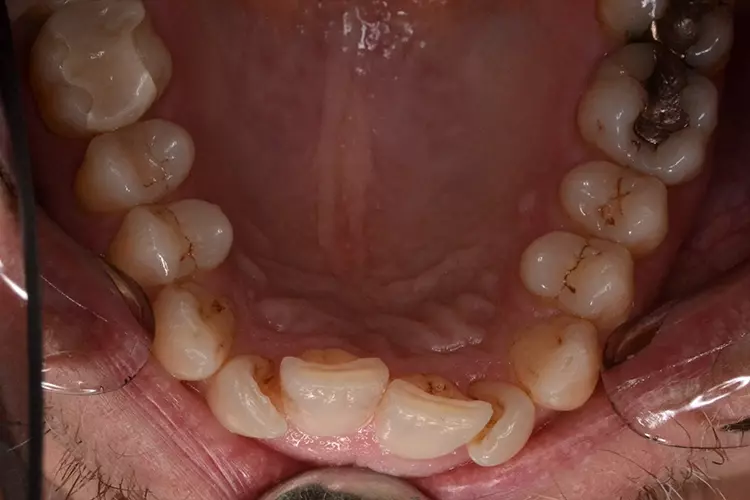

Bei dem heute 49-jährigen Patienten wurde seit Kindertagen versäumt, die Ober- und Unterkieferzahnbögen kieferorthopädisch auszurichten. Der Patient leidet seitdem stark unter seinen Zahnfehlstellungen.

Die Fraktur des stark elongierten Zahnes 21 war für den Patienten der Ausgangspunkt, sowohl die Front des Ober- als auch des Unterkiefers prothetisch überarbeiten zu lassen. Dabei wurde der frakturierte Zahn 21 durch ein navigiert eingesetztes Sofortimplantat ersetzt, während die verschachtelt stehenden Zähne 12 und 42 durch eine Brückenversorgung korrigiert wurden (Abb. 4a-j).